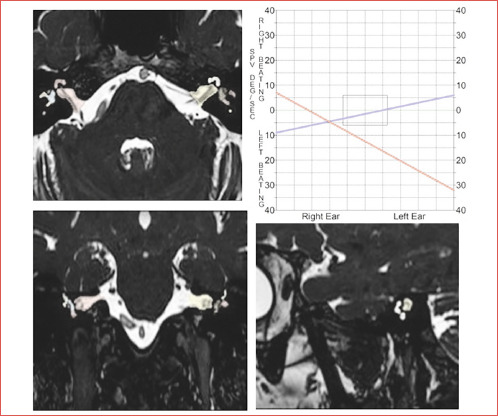

Methods: 26 patients with unilateral vestibulocochlear deficits underwent hearing and vestibular assessments and were categorised into severity classes using audiological and vestibular deficit scores. Normalised signal intensity values of inner ear structures were extracted from 3D-T2-WI-MRI scans (nT2mean, nT2Max, nT2min) and signal intensity ratios were calculated using the unaffected ear as a reference.

Results: Asymmetry ratios of nT2Max and nT2mean volumetric intensity values from the cochlea and entire inner ear discriminated severe hearing impairment from lesser deficits and diagnostic performance of nT2mean values was excellent.

Conclusions: Quantitative MRI analysis may be a useful tool to assess the severity of auditory deficits. Asymmetry ratios of nT2mean and nT2Max signal intensity values derived from the cochlea and entire inner labyrinth are surrogate indicators of unilateral cochlear-vestibular deficits and may have potential prognostic value.